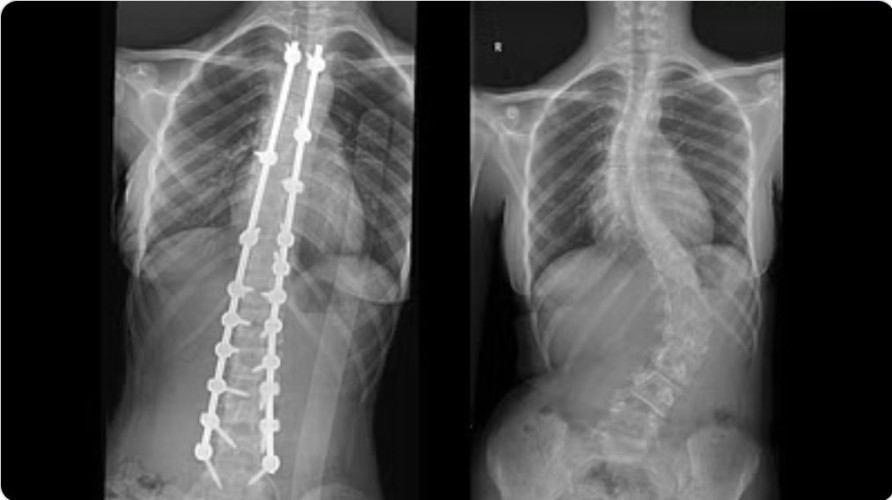

وأكد الدكتور عوض أن نتائج الفحوصات أشارت إلى وجود اعوجاج شديد في منطقة الفقرات القطنية شديد، تبلغ زاويته 76°، بالإضافة إلى تقوّس آخر في الفقرات الصدرية بلغ انحناؤه 58°، مع تشوّه وبروز في منطقة الصدر والبطن، مشيرًا إلى أن الفريق الطبي المعالج قام بدراسة وافية للحالة، وقرّر التدخُّل الجراحي للحدّ من المضاعفات المتمثّلة في ازدياد شدة التقوسات بالعمود الفقري، والأعراض المصاحبة له في حالة التأخر بالعلاج.

وأضاف الدكتور عوض أنه تم استخدام أجهزة وتقنيات متطورة للمساعدة في تعديل وتقويم الفقرات، في عملية استغرقت 3 ساعات، وتم فيها تعديل الجنف بنسبة 100% للفقرات القطنية، وبنسبة 96% لفقرات الصدر، علاوة على تعديل وتقويم عظام الحوض بصورة جيدة. ولله الحمد تكلَّلت جهود الفريق الطبي بالنجاح دون أية مضاعفات، وقد استطاعت الفتاة ولله الحمد الوقوفَ والمشي في الساعات الأولى بعد العملية، وخرجت من المستشفى في اليوم الرابع وهي بصحة جيدة، وقد انتهت لديها كافة الأعراض السابق ذكرها.